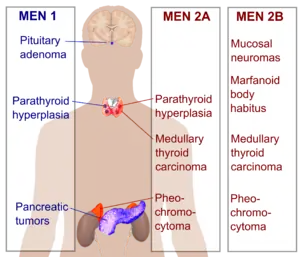

Multiple endocrine neoplasia (abbreviated MEN) is a condition which encompasses several distinct syndromes featuring tumors of endocrine glands, each with its own characteristic pattern. In some cases, the tumors are malignant, in others, benign. Benign or malignant tumors of nonendocrine tissues occur as components of some of these tumor syndromes.

A useful mnemonic to remember the associated neoplasias is below:

MEN I (3 Ps) - Pituitary, Parathyroid, Pancreatic

MEN IIa (2Ps, 1M) - Pheochromocytoma, Parathyroid, Medullary Thyroid Ca

MEN IIb (1P, 2Ms) - Pheochromocytoma, Medullary Thyroid Ca, Marfanoid habitus/mucosal neuroma

Manifestations

Multiple Endocrine Neoplasia type 1 (MEN1) is a rare hereditary endocrine cancer syndrome characterized primarily by tumors of the parathyroid glands (95% of cases), endocrine gastroenteropancreatic (GEP) tract (30–80% of cases), and anterior pituitary (15–90% of cases).[19] Other endocrine and non-endocrine neoplasms including adrenocortical and thyroid tumors, visceral and cutaneous lipomas, meningiomas, facial angiofibromas and collagenomas, and thymic, gastric, and bronchial carcinoids also occur. The phenotype of MEN1 is broad, and over 20 different combinations of endocrine and non-endocrine manifestations have been described. MEN1 should be suspected in patients with an endocrinopathy of two of the three characteristic affected organs, or with an endocrinopathy of one of these organs plus a first-degree relative affected by MEN1 syndrome.